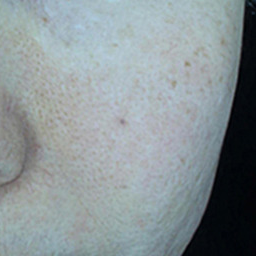

내원 당시 환자분의 마크뷰 사진

환자분은 전반적으로 피부가 칙칙하고 붉으며, 모공이 넓고 결이 거친 상태였습니다.

이를 정확하게 파악하기 위해 피부진단기 마크뷰(Mark-VU)로 촬영했는데요. 일반광, 편광, 광택광, 자외선광 총 4가지 광원을 이용해 육안으로 보기 어려운 피부 속 문제까지 정밀하게 확인했습니다.

잔주름 / 넓은 모공 / 홍조

홍조 – 혈관 확장으로 인한 전반적인 붉은기

거친 피부결 – 탄력 저하와 각질 비정상 탈락

넓은 모공 – 콜라겐 감소로 인한 피부 지지 구조 약화

미세 잔주름 – 피부 수분 및 탄력 저하

위와 같은 복합적인 문제들이 발생한 상황입니다.